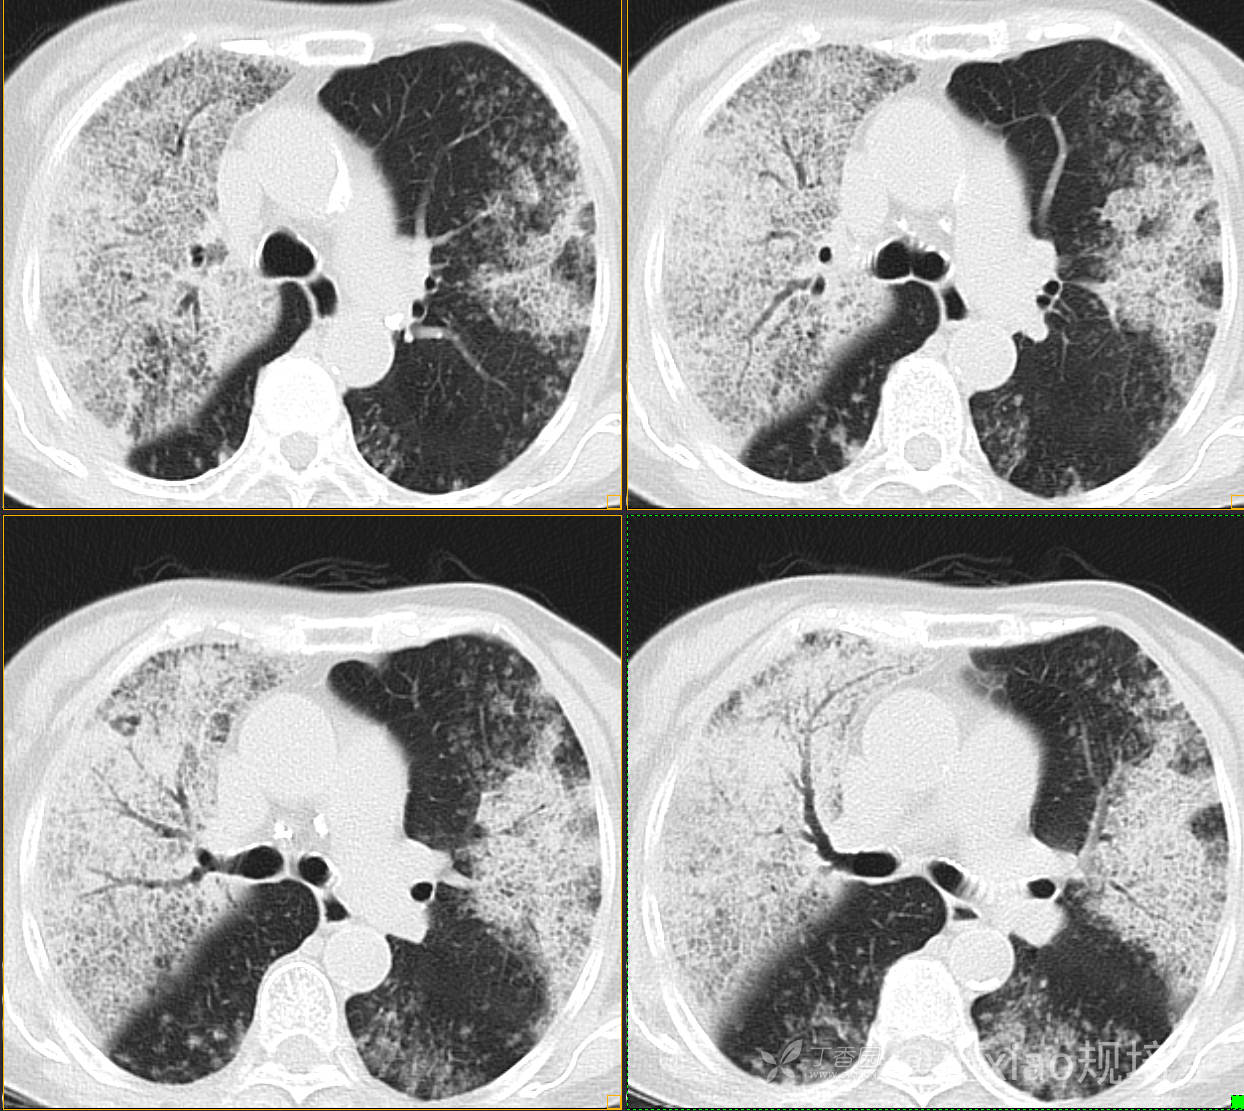

患者,女,89岁

咳嗽,咳痰一月余

肺泡蛋白沉着病 (19)

腺癌 (183)

弥漫性囊性肺病 (9)